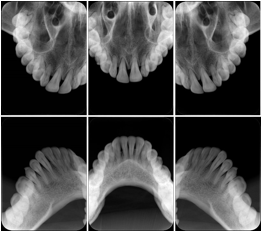

1. A patient in rural Canada visits a general ophthalmologist and is found to have diabetic macular edema. The general ophthalmologist would like to discuss the case with a retina specialist before performing laser surgery. A fluorescein angiogram is done with multiple retinal images taken in a timed series after an intravenous injection. The images along with a Structured Display are shared via a Health Information Exchange with a retina specialist in Calgary, who opens them using his Ophthalmology EMR software and consults via phone with the general ophthalmologist. Both physicians view the images in the same layout so the retina specialist can provide accurate guidance for treating the patient.

2. A patient in rural Iowa visits his primary care physician for management of diabetes. Three non-mydriatic (patient's eyes are not dilated) photographs are taken of the back of each eye, and forwarded electronically along with a Structured Display to an ophthalmologist in Iowa City. The ophthalmologist reads the photos in an agreed upon layout so there is no mistake about what portion of which eye is being viewed. The ophthalmologist is able to tell the primary care physician that his patient does not need to come to Iowa City for face to face ophthalmologic care, but that there is a particular view of the left eye that should be photographed again in 6 months.

Ophthalmic Retinal Study Structured Display

Figure OO-3. Ophthalmic Retinal Study Structured Display